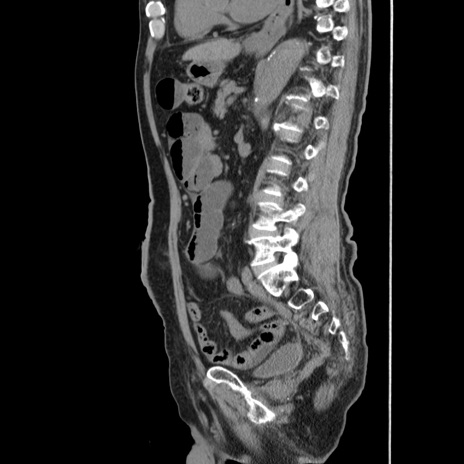

症例24(矢状断像)

【症例】80歳代男性

【主訴】左側腹部痛、嘔吐

【現病歴】本日早朝より左腹部に痛みあり。昼頃嘔吐認めたため、救急要請。

【既往歴】直腸癌(Mile手術)、胆摘

【身体所見】意識清明、BT 35.9℃、BP 221/93mmHg、SpO2 97%(RA) 、腹部:左ストーマ周囲に限局性の腹部膨隆あり。 膨隆部自発痛・圧痛あり・軟。

【データ】WBC 7700、CRP 0.09